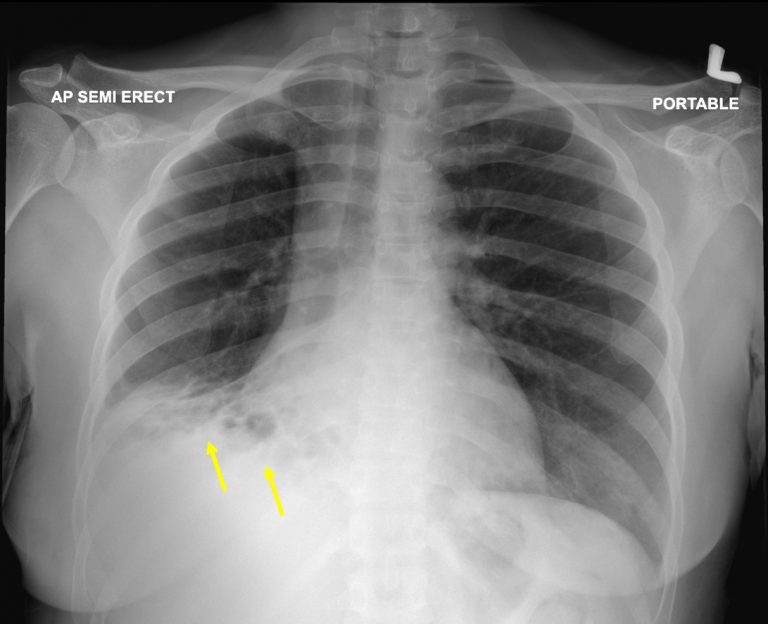

Chest radiograph shows central bronchiectasis (arrow) i Openi Bronchiectasis Chest X Ray Radiopaedia Findings include bronchial diameter exceeding that of the adjacent pulmonary artery and lack of normal tapering of terminal bronchioles as they course toward the lung periphery. A bronchiectatic airway can show abnormal widening and thickening of its airway wall. chest radiography is usually the initial study performed in suspected bronchiectasis. diagnosis of bronchiectasis is usually made using chest. Bronchiectasis Chest X Ray Radiopaedia.